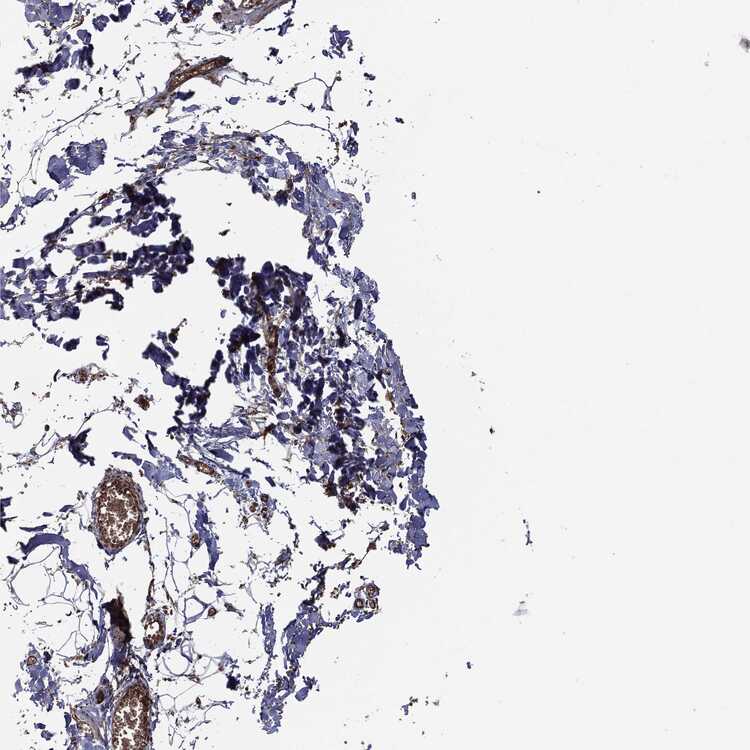

SOFT TISSUE 1 - Antibody stainingi

Antibody staining in the annotated cell types in the current human tissue is reported as not detected, low, medium, or high, based on conventional immunohistochemistry profiling in selected tissues. This score is based on the combination of the staining intensity and fraction of stained cells.

Each image is clickable and will lead to virtual microscopy that enables deeper exploration of all samples and also displays staining intensity scores, fraction scores and subcellular localization as well as patient and tissue information for each sample.

Antibody HPA019795Antibody HPA063893Antibody CAB003845

Chondrocytes Not detected--

Fibroblasts Not detectedMediumNot detected

Peripheral nerve --Not detected

SOFT TISSUE 2 - Antibody stainingi

Peripheral nerve Not detectedLowNot detected